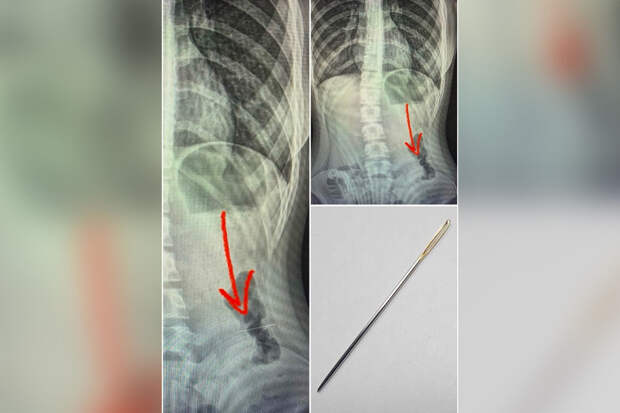

Пострадавшего доставила в больницу бригада скорой помощи, в ходе обследования врачи обнаружили, что игла застряла в кишечнике."Под общим обезболиванием, при проведении диагностической колоноскопии было обнаружено и удалено инородное тело в средней трети нисходящего отдела ободочной кишки", — рассказали в больнице.

Иглу удалось успешно извлечь, жизни и здоровью ребенка ничего не угрожает.